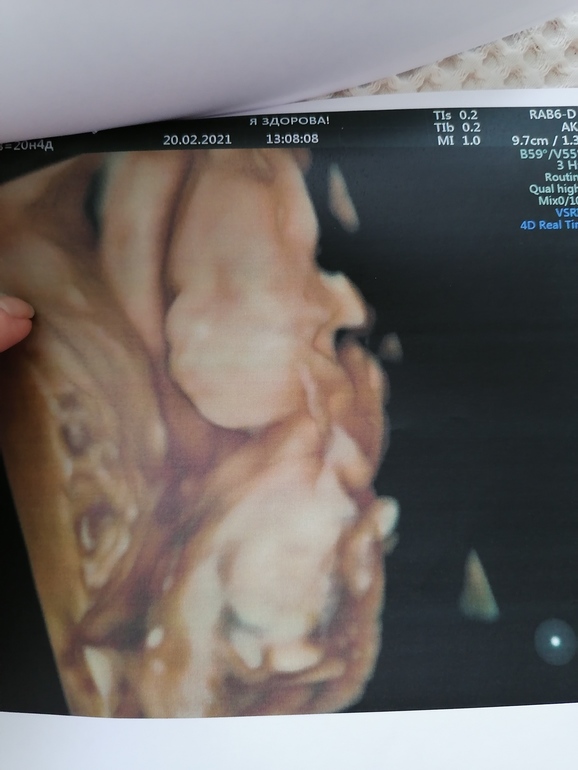

УЗИ прошло шикарно, врач меня вспомнила, все расспросила как и что. Всё рассмотрела идеально. Муж сидел с открытым ртом. Сделали нам аж 15 фото, прям фотосессия была у сыночка🥰😉. Он так мило зевал, язычком водичку ловил💙💙💙. Прям умиление сплошное🥰. Лежит головой вниз.

Ну и наши фоточки🥰👶🙏🙏🙏.

Ну и фотосессия сыночка👶🙏🙏🙏🥰.